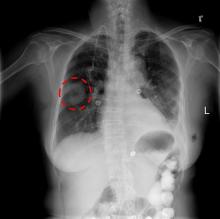

A team of researchers including investigators from Mayo Clinic has identified a technology to address the problem of false positives in computed tomography (CT)-based lung cancer screening. The team’s findings are published in the current issue of PLOS One.